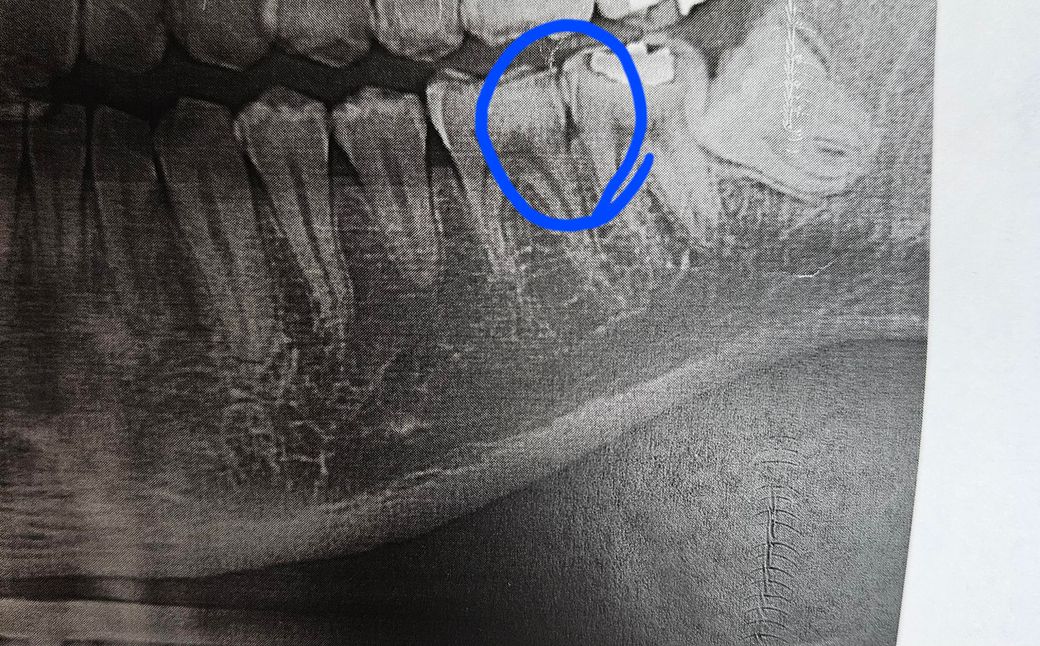

파랑색 동그라미부분 인접면충치일까요? 일단 치과의사가 충치가 있다는 얘기는 안 했습니다. 따로 걱정할 필요가 없는 건가요??

파노라마 상으로는 충치가 잇는건 아닌거 같습니다. 치아 사이 공간이 까맣게 보이는거 같습니다.

치아 사이의 충치는 치근단 사진에서 보다 명확히 나타나며 , 파노라마는 왜곡이 있습니다.

사진상 봤을때 충치는 아니고 치경부소환(cervical burn out)증상으로 보입니다.

인접면 충치는 아닌 것으로 보이며 인접면에서 x-ray 상이 중첩되면 검게 보이는 경우가 대부분입니다. 혹시 모르니 6개월 후 다시 확인하는 것이 좋습니다.